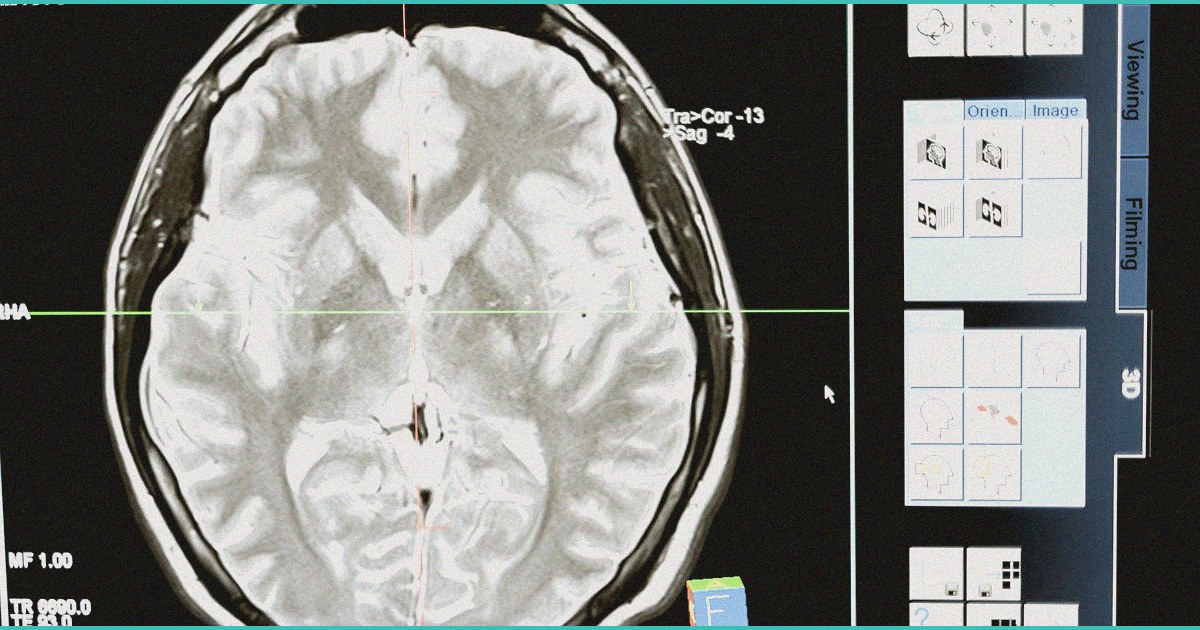

Clinical Context

Background information relevant to the evolving cannabis medicine landscape.